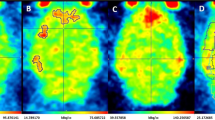

In vivo uptake of 99mTc-omberacetam was investigated; SPECT imaging revealed a rapid radiotracer distribution throughout the various tissues and body organs of the Swiss albino mice (Table 1).

The pharmacokinetic profile of 99mTc-omberacetam, a potential radiopharmaceutical, was assessed at different time intervals. At 5 min p.i., the blood uptake (22.3 ± 0.5% ID/g) was initially high but slowly decreased within 120 min p.i. to 6.2 ± 0.2% ID/g, likely due to binding to plasma proteins. The liver showed ID/g relatively high uptake of 10.4 ± 0.7% at 30 min p.i., which might result from hepatic omberacetam metabolization. Whereas the omberacetam labeled drug was mainly excreted by the kidneys and, consequently, with time, the uptake increased to an ID/g of 15.8 ± 0.2% and remained high over time in comparison to that in further body organs. At 5 min p.i., the 99mTc-amberacetam had highly ID/g accumulated in the brain (8.9 ± 0.1%); thereafter, the uptake of ID/g levels decreased to 7.4 ± 0.2, 5.7 ± 0.2, 4.5 ± 0.1, and 2.4 ± 0.1% at 15, 30, 60, and 120 min p.i., respectively. Additionally, the brain to blood ratio was calculated to assess the relative uptake in the brain compared to that in the bloodstream. The %ID/g uptake brain to blood ratios were 0.39, 0.53, 0.58, 0.54, and 0.38 at 15, 30, 60, and 120 min p.i., respectively. The radioactivity in the other organs was within the normal range (Fig. 7).